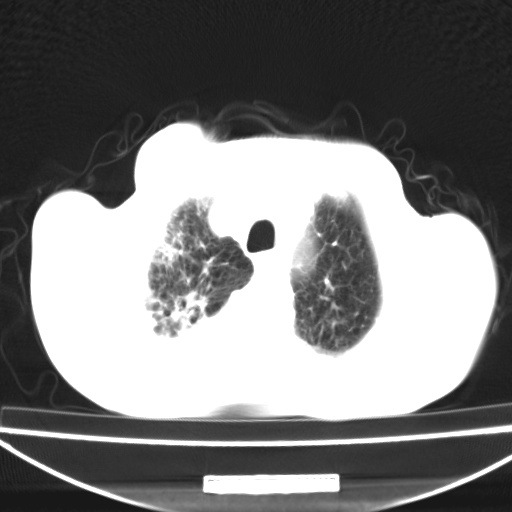

标题: CT13796:请会诊右上费病变!

患者男80岁,反复咳嗽多年,咳喘伴咯血1月

右上肺周围型肺癌伴肺门淋巴结转移.右上肺继发型肺结核.

右上肺周围型肺癌伴肺门淋巴结转移

右肺上叶占位性病变,考虑周围型肺癌,肺门淋巴结转移。要是能提供更多的临床资料就好了,以供鉴别诊断。

右肺尖周围型肺癌伴肺门淋巴结肿大

右肺上叶占位性病变,考虑周围型肺癌,肺门淋巴结转移。

右上肺周围型肺癌伴肺门、纵膈淋巴结转移

考虑为:右肺上叶肺癌伴阻塞性肺炎、右肺门及纵膈淋巴结转移。

右上肺结核合并右上肺癌,肺门淋巴结肿大